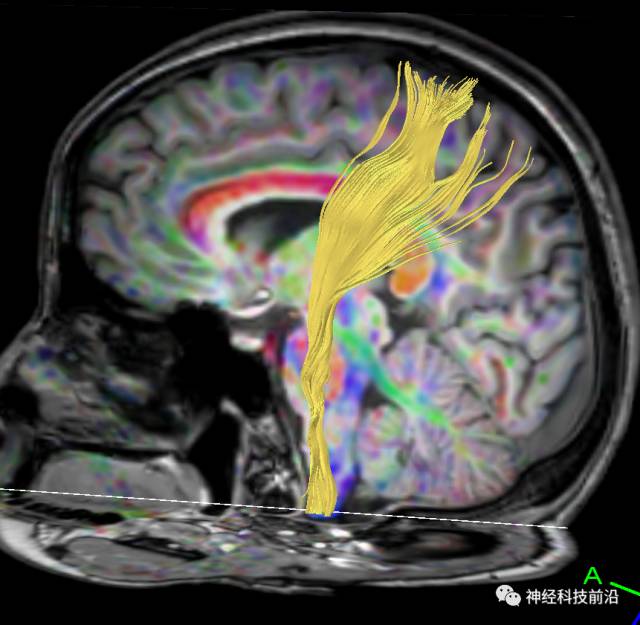

下面为皮质脊髓束的走形及位置